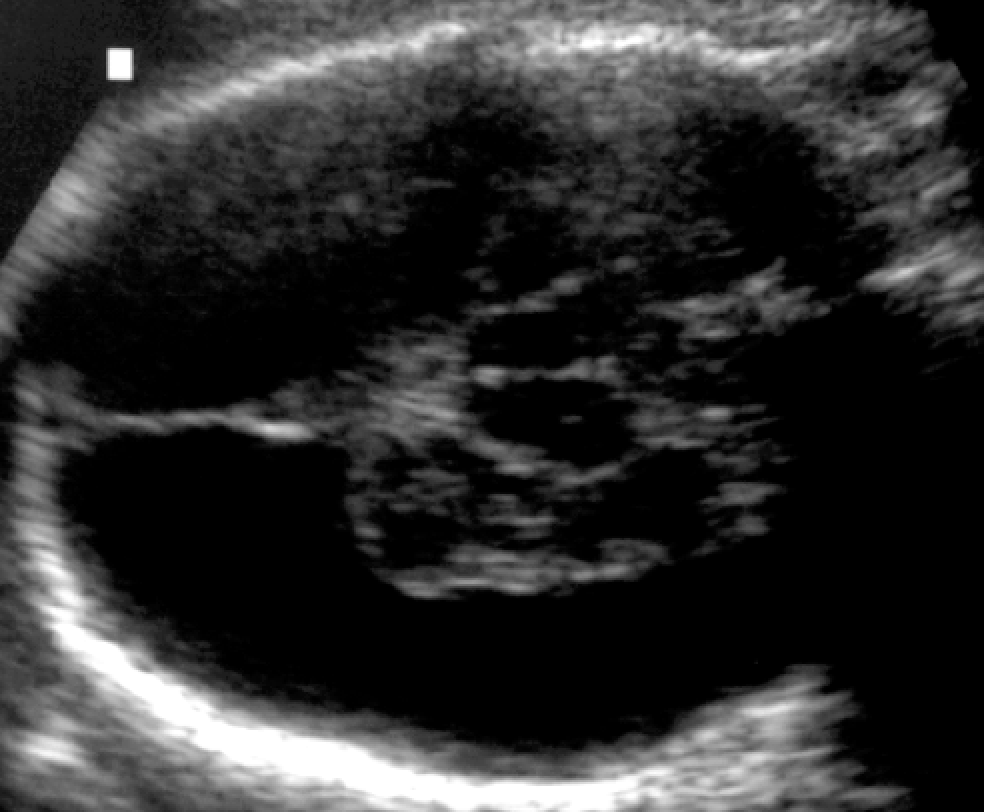

Baby born to mother with hypercoagulable disorder

Diagnosis?

Etiology?

Hydranencephaly

No cerebral hemispheres visualized

but Falx, thalami, and midbrain are intact

In-utero ACA and MCA strokes